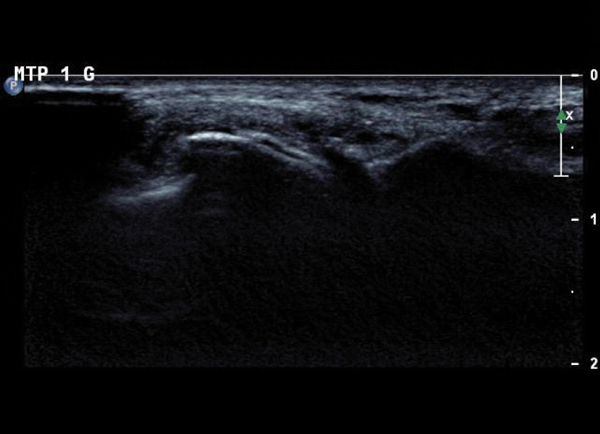

Échographie de la 1re métatarsophalangienne. Aspect dit en « double contour », correspondant à des dépôts uratiques à la surface des cartilages hyalins et un aspect de synovite en « tempête de neige » chargée en cristaux d’urate. Tiré de : Chalès G, Guggenbuhl P. Arthropathie microcristalline. Rev Prat 2013;63(5):709-20.